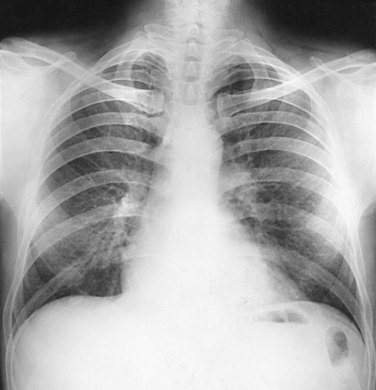

For radiography of the heart and lungs, the patient is placed in an upright position whenever possible to prevent engorgement of the pulmonary vessels and to allow gravity to depress the diaphragm. Of equal importance, the upright position shows air and fluid levels. In the recumbent position, gravitational force causes the abdominal viscera and diaphragm to move superiorly; it compresses the thoracic viscera, which prevents full expansion of the lungs. Although the difference in diaphragm movement is not great in hyposthenic individuals, it is marked in hypersthenic individuals. Figs. 10-10 and 10-11 illustrate the effect of body position in the same patient. The left lateral chest position (Fig. 10-12) is most commonly employed because it places the heart closer to the IR, resulting in a less magnified heart image. Left and right lateral chest images are compared in Figs. 10-12 and 10-13.

Structures shown: An AP projection of the thoracic viscera (Fig. 10-51) shows an image similar to the PA projection (Fig. 10-52). Being farther from the IR, the heart and great vessels are magnified and engorged, and the lung fields appear shorter because abdominal compression moves the diaphragm to a higher level. The clavicles are projected higher, and the ribs assume a more horizontal appearance.